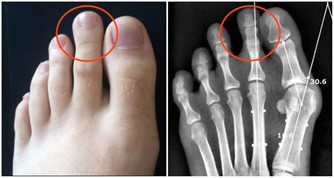

除了手部,腿上也容易出現青筋,這種情況不要忽視,有可能是靜脈曲張的預兆,尤其是過度勞累和久坐以及久站的人需要多加註意。不要總保持一個姿勢,要適當活動活動,改善一下血液循環。